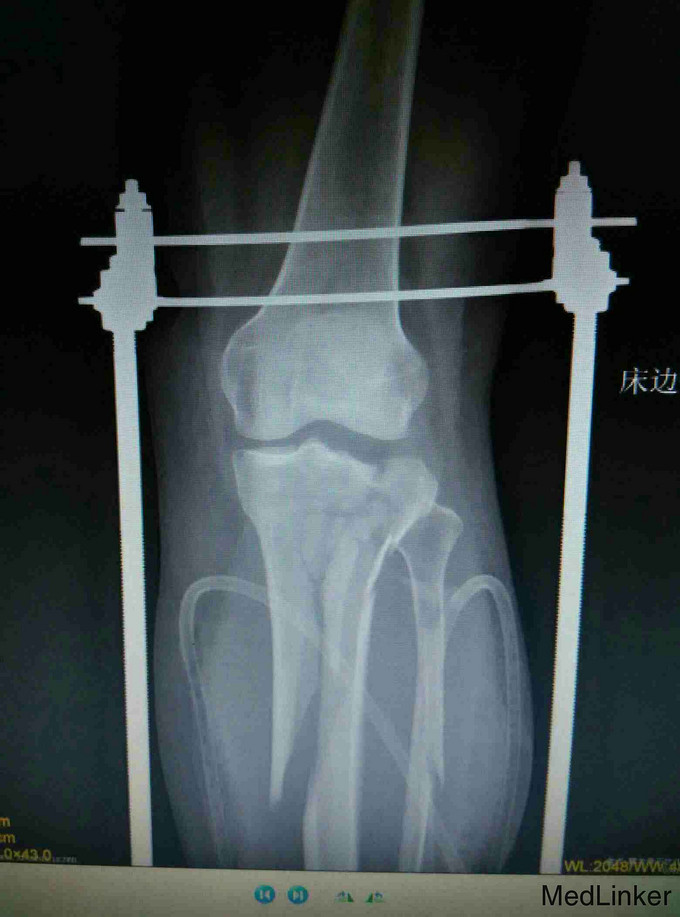

考虑为筋膜室综合征,予急诊行切开减压,考虑一期骨折复位内固定手术风险高,则行骨折端外固定架固定,同时VCD引流,待局部肿胀减轻,局部无明显张力,伤口无炎性反应后,二期行开放复位钢板固定术。